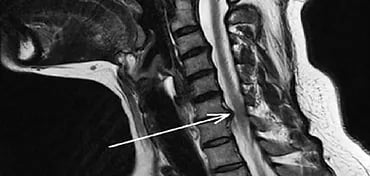

You might have heard the words “herniated disc” or “slipped disk”, a condition when the gel-like fluid in the centre of a spinal disc pushes out through the weak spot in the tough outer wall. Similarly, cervical disc prolapse is the herniation that occurs in the cervical spine.